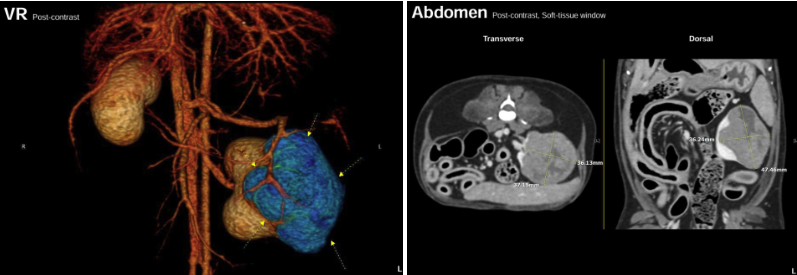

폼피츠 강아지 환자는 타 병원에서 건강검진 중에 초음파검사를 통해 신장 종양으로 의심되는 MASS(덩어리)가 발견되었습니다. 정확한 크기와 위치 확인을 위해 CT 촬영과 신장종양 세포검사를 진행하였으며, 검사 결과 신장세포암종(RCC: Renal Cell Carcinoma)로 잠정진단 되었습니다.

또한 좌측 신장과 인접한 림프절 비대 소견도 확인되어 전이도 의심되는 상황이었습니다. 보호자님께서는 상담 후 종양 제거를 위한 수술을 결정하시게 되었고, 종양 수술을 위해 에스동물메디컬센터 양산점으로 내원하시게 되었습니다.

강아지 신장암 CT영상 : 종양성 변화를 보이는 좌측 신장

강아지 신장암 CT영상: 비대된 림프절과 정상크기의 부신